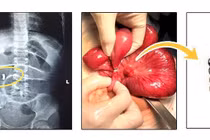

Chỉ nhờ mổ kịp thời, bé trai Hà Nội đã thoát khỏi nguy cơ tắc ruột do nuốt phải hạt nhựa có khả năng trương nở trong ruột, cảnh báo nguy hiểm từ đồ chơi.